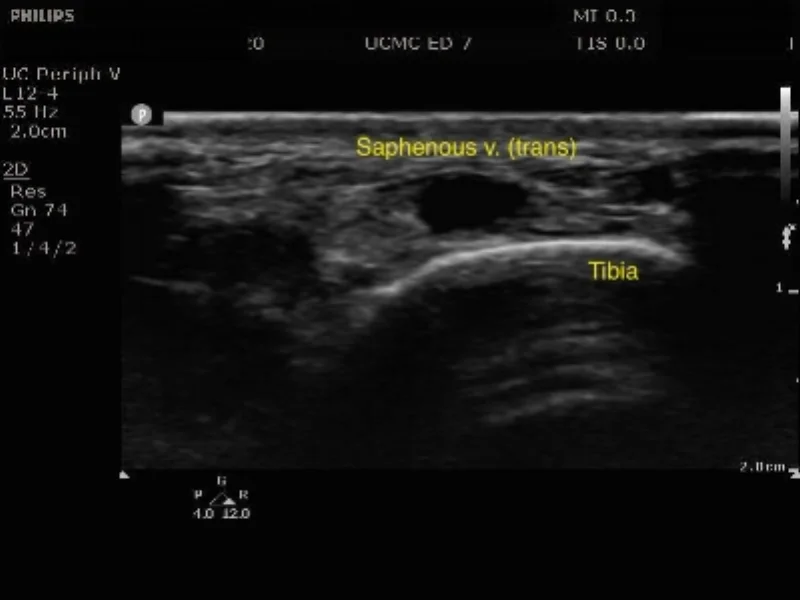

Cannulation in the transverse Plane

When selecting the site be sure to do a preliminary scan of both legs to identify the best target. In addition to applying a tourniquet, saphenous vein diameter is shown to increase with the patient placed in reverse trendelenburg position (5). Cannulation can be performed with the probe in either the transverse or long axis orientation depending on the operator’s level of experience and comfort.

Cannulate the vein in either the transverse or longitudinal plane as seen above.

For a transverse approach pierce the skin about 0.5cm from the probe at a 30-45 degree angle to the skin. The needle tip will appear as a bright white dot on your screen, and once you see this you should stop moving the needle. Sweep the probe forward until the dot disappears then stop moving the probe Advance the needle until you see the bright dot of the tip reappear, and continue to advance towards your target in a stepwise fashion until your needle is in the center of the vessel lumen and you have flash in the needle chamber.